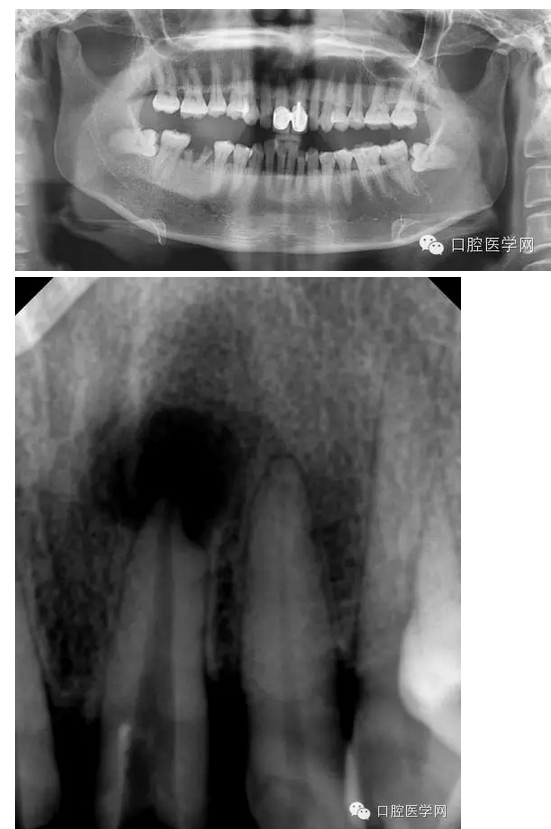

左上1根尖膿腫患者

檢查:21相對應(yīng)的前庭溝隆起,粘膜紅腫,有波動感,門診(+),叩(++)。

輔助檢查:21x線示根周有大面積陰影

診斷:21急性根尖周炎